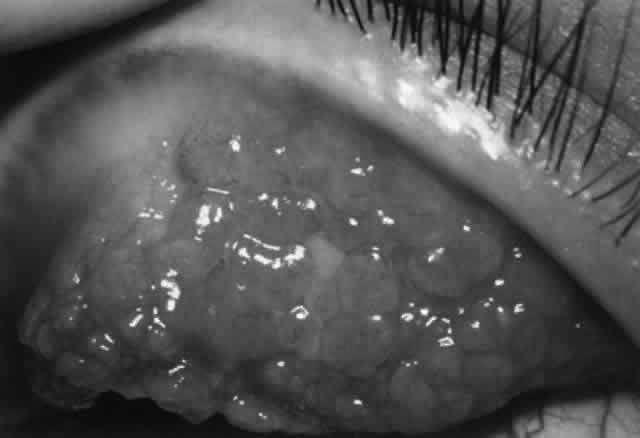

Treatment includes removal of the offending agent (including discontinuing eye drops) or avoidance (use of protective wear such as goggles, worksuits). In the acute stage of periocular contact dermatitis, cool compresses and topical nonfluorinated corticosteroids (e.g., hydrocortisone, desonide) can be used. In some cases, especially if severe, unresponsive to therapy, or associated with cutaneous ulcerations, cultures should be performed to rule out secondary infectious eczematoid dermatitis (usually staphylococcal or streptococcal in origin). Chronic periocular dermatitis requires maintenance of skin hydration and topical corticosteroids. In some cases (either acutely severe or chronic and unresponsive cases), a course of oral prednisone may be indicated. Contact conjunctivitis/keratitis may be soothed by application of nonpreserved artificial tears. A short course of topical corticosteroids may speed recovery, but one always should consider the possibility of further sensitization by the vehicle or the steroid itself.

MICROBIOALLERGIC DISEASE

Catarrhal Infiltrates and Ulcers

Catarrhal infiltrates typically occur in association with chronic staphylococcal blepharoconjunctivitis and are located in the peripheral cornea, separated from the limbus by a lucid interval. They are most commonly found at the two, four, eight, and ten o'clock positions, where the lid margins cross the peripheral cornea. These infiltrates are gray-white in color, may be single or multiple, and spread circumferentially rather than centrally, sometimes making partial rings. Overlying superficial ulceration often develops. There may be associated conjunctival injection or mild anterior chamber reaction. Symptoms include irritation, tearing, pain, and photophobia. Catarrhal ulcers are more common in adults than in children (compare with phlyctenulosis).